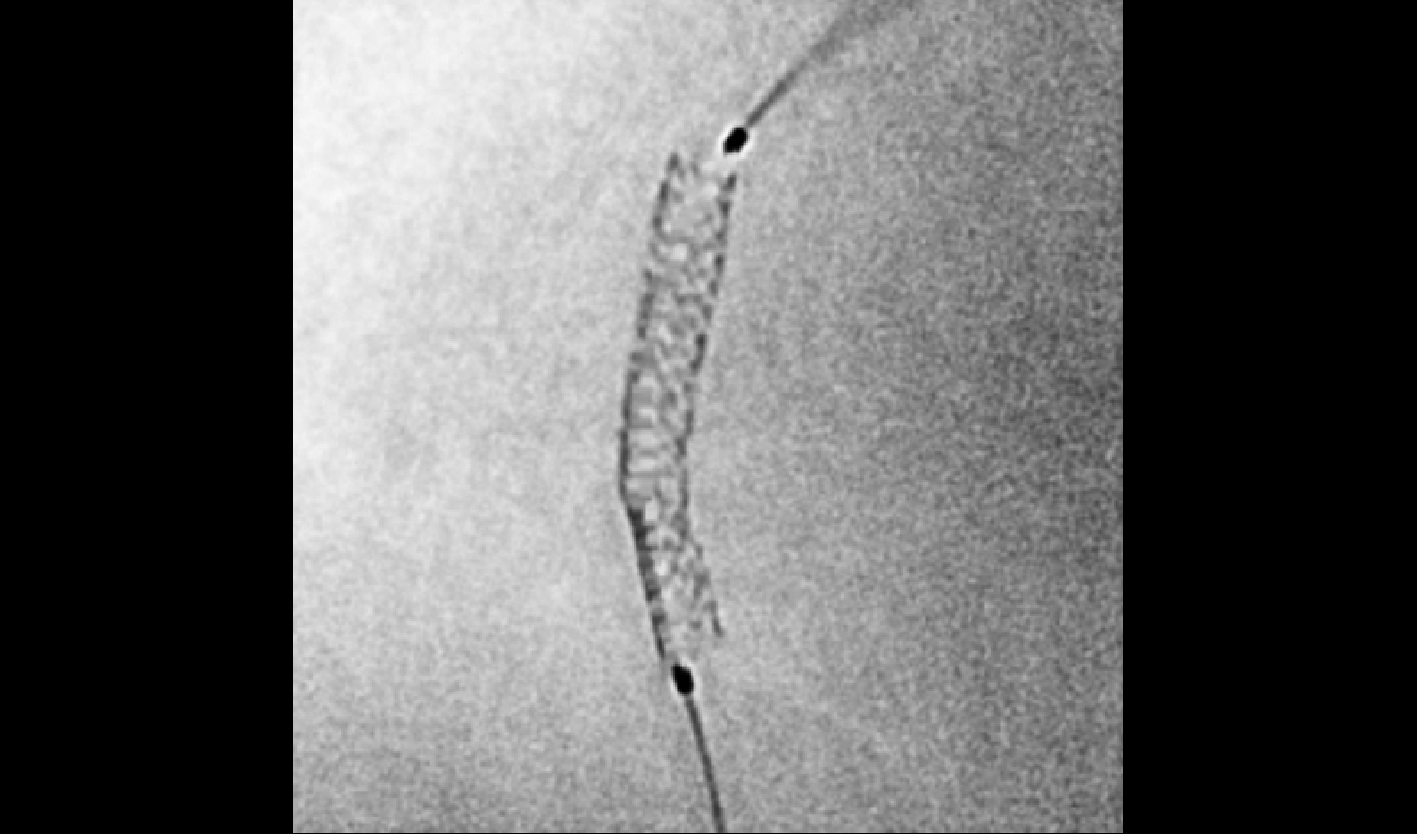

Quantum 3D/Quantum CT/Quantum Stent

2K超清影像链,精至微小血管一览无余

分辨率高